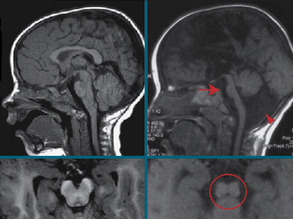

Battling Brain Breakdown